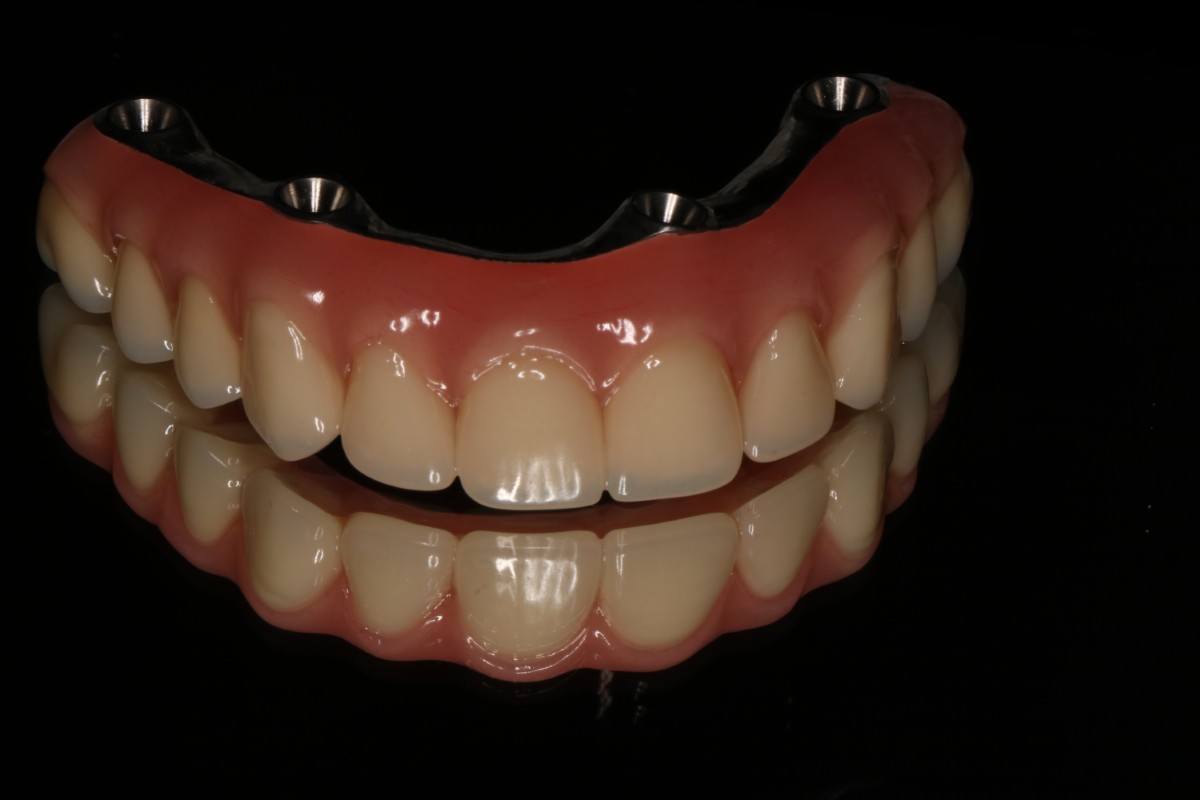

1. Proteza wykonana wg protokołu All On X

Metoda All On X to rewolucyjne podejście do odbudowy całej szczęki na implantach. Polega na osadzeniu pełnej protezy stałej na odpowiedniej liczbie implantów (zwykle 4-6), strategicznie rozmieszczonych w kości szczęki lub żuchwy. Liczba implantów jest dobierana indywidualnie do każdego pacjenta – stąd nazwa “All On X”, gdzie X oznacza optymalną dla danego przypadku liczbę wszczepów.

Proteza wykonana w technice All On X może przez długi okres funkcjonować jako uzupełnienie samodzielne i jest najczęściej wstępem do wykonania stałych uzupełnień protetycznych np. mostów porcelanowych przykręcanych dna implantów

Efekty leczenia

Przypadek 1

Przypadek 2